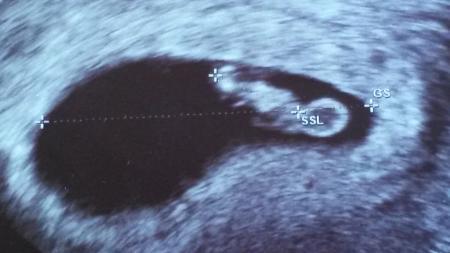

Hallo Mädels! Ich war heute Vormittag bei meiner FÄ , weil ich am Samstag und Sonntag etwas Blut am Papier hatte. Zum Glück ist alles in Ordnung. Mumu zu, keine Verletzungen erkennbar, Abstrich war auch super und das Baby ist gut gewachsen und das Herzchen schlägt kräftig. Aber wo die Blutschlieren herkamen, ist nicht raus... Ich soll jetzt früh und abends Magnesium nehmen und öfter die Beine hoch legen und Stress vermeiden. (soweit das mit einem 2,5 jährigen Wildfang möglich ist ) Jetzt bin ich erst mal beruhigt, dass es dem Baby gut geht!!!! Und ein neues kleines Bildchen hab ich sogar auch bekommen. Nun hoffe ich, dass alles gut bleibt und ich nicht noch mal so einen riesen Schreck bekomme.....

:) Baby und Dottersack